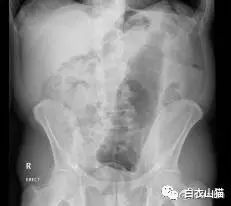

第4天,他拉不出大便。剧烈呕吐,剧烈腹痛。实在熬不住了,就去了一个大医院,但是,他隐瞒了自己把黄鳝塞进菊花的病史。

医生给他检查的时候,发现已经有腹膜炎症状,怀疑肠梗阻,拍了个片子,就是上面那个片子:一条大黄鳝在肚子里。

考虑到他已经有腹膜炎的症状,说明肠子已经有个地方破了。只能动手术了。